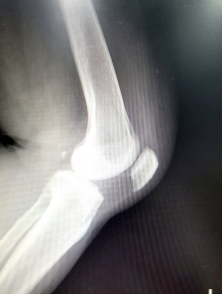

슬개골은 대퇴골과 종아리뼈 사이에 위치한 삼각형 모양의 큰 뼈로 대퇴골과 함께 무릎 관절을 구성합니다. 슬개골은 대퇴골에 연결된 근육과 인대에 의해 위치가 고정되어 있으며, 무릎 관절에서 일어나는 움직임에 중요한 역할을 합니다. 슬개골의 이상 발생 시 무릎 통증, 팽만, 무릎이 튀어오르는 증상 등이 발생할 수 있습니다.

슬개골 연골연화증은 슬개골과 대퇴골 사이에 위치한 슬개골연골이 변성되어 파손되거나, 연화되는 질환입니다. 대개 중년 이상의 여성에서 발생하며, 골다공증, 슬개골 이상운동, 유전적 요인 등이 원인으로 작용합니다. 증상으로는 슬개골 통증, 불안정성, 퇴행성 변화 등이 나타납니다. 진단은 X선, MRI, 초음파 등을 이용하여 확인할 수 있으며, 치료는 보존적 치료(약물 치료, 근력강화 운동 등)와 수술적 치료(슬개골 전방 이동술, 전·후방 상처 수술 등)으로 이루어집니다. 빠른 진단과 치료가 필요하며, 치료를 받지 않으면 슬개골 골관절염, 연골 파괴 등 심각한 합병증이 발생할 수 있습니다.